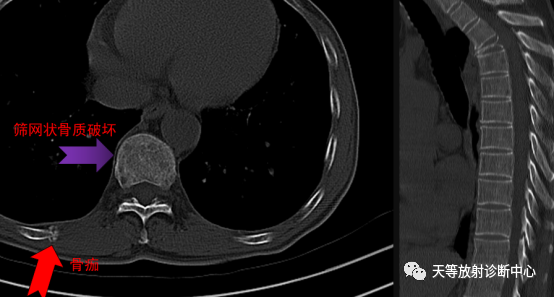

3、病灶周围骨皮质不规则吸收、缺如,部分残留骨皮质硬化,在 CT图像上呈筛孔状、穿凿状破坏,见周围可见明显软组织块影,主要表现为骨质破坏区软组织块影从骨皮质缺损处向周围侵犯。

▲上图:晒网状骨质破坏区以及肋骨的病理性骨折骨痂形成。